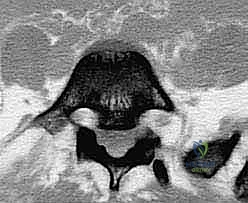

- التصوير بالرنين المغناطيسي (MRI): هو المعيار الذهبي لرؤية الأنسجة الرخوة. يوضح بدقة متناهية حالة الأقراص الغضروفية، ومقدار الاختناق في القناة الشوكية، والضغط الواقع على جذور الأعصاب.

1. تخفيف الضغط العصبي (Decompression / Laminectomy)

الخطوة الأولى والأهم هي إزالة الضغط عن الحبل الشوكي والأعصاب. يتم ذلك من خلال استئصال الصفيحة الفقرية (Laminectomy) وإزالة الأربطة المتضخمة (Ligamentum Flavum) وأي أجزاء من الغضروف المنزلق تضغط على الأعصاب. يتم إجراء هذه الخطوة تحت الميكروسكوب الجراحي لضمان عدم المساس بالأغشية العصبية الرقيقة (Dura Mater). بمجرد تحرير الأعصاب، يزول سبب الألم الجذري (عرق النسا) فوراً.

3. دمج الفقرات بين الأجسام الفقرية (PLIF / TLIF)

في حالات الانزلاق عالي الدرجة، غالباً ما يتطلب الأمر دعماً إضافياً من الأمام (بين أجسام الفقرات). هنا يتألق الدكتور هطيف باستخدام تقنيات (PLIF - Posterior Lumbar Interbody Fusion) أو (TLIF - Transforaminal Lumbar Interbody Fusion).

في هذه التقنية، يتم استئصال القرص الغضروفي التالف بالكامل، ووضع قفص داعم (Cage) مصنوع من مادة الـ PEEK أو التيتانيوم، ومملوء بالطعوم العظمية، في مكان الغضروف. هذا الإجراء يعيد الارتفاع الطبيعي للفقرات، ويفتح مسارات الأعصاب بشكل ممتاز، ويوفر نسبة نجاح للدمج العظمي تقارب 100% لأنه يضع العظم في منطقة تتحمل ضغطاً ميكانيكياً عالياً مما يحفز نمو العظام.